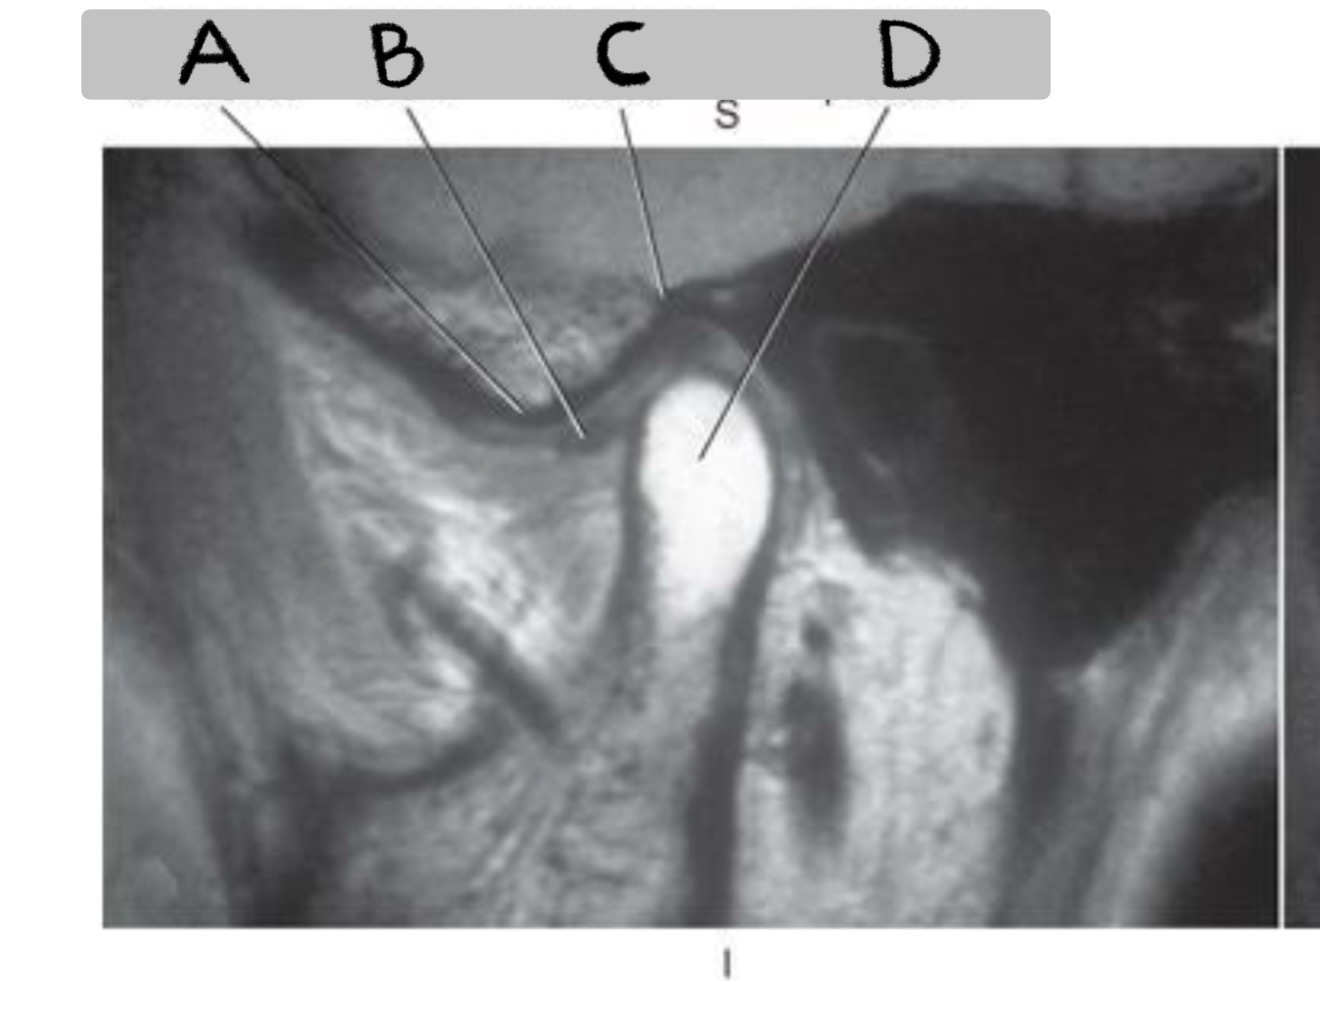

Q

MATCH

Mandibular fossa

Condyloid process

Articular eminence

Articular disk

A

C - Mandibular fossa

D - Condyloid process

A - Articular eminence

B - Articular disk

What plane

Sagittal oblique TMJ (closed vs. open mouth)